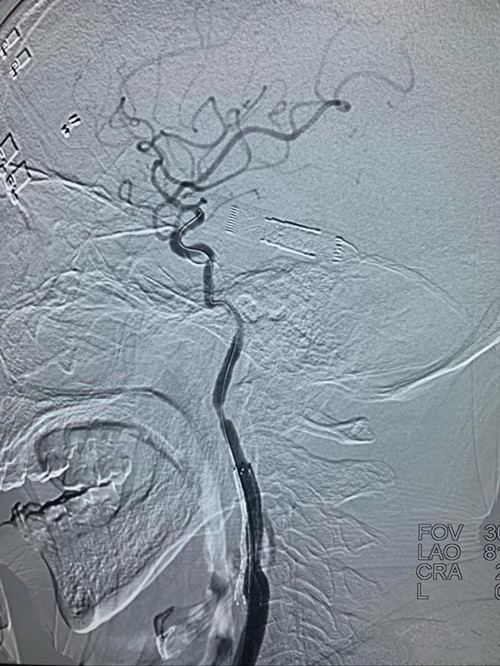

经取栓治疗后,原本闭塞不通的右颈内动脉-右大脑中动脉变得通畅无阻,但右颈内动脉闭塞处经球囊扩张成型后仍存在严重的“一线天”重度狭窄,随时可能在发生闭塞,与家属沟通后,决定为患者进行右颈内动脉支架植入彻底治疗病变。

右颈内动脉支架定位后释放支架,血管成型良好。

正侧位造影显示右颈内动脉-右大脑中动脉开通良好,血流恢复正常。